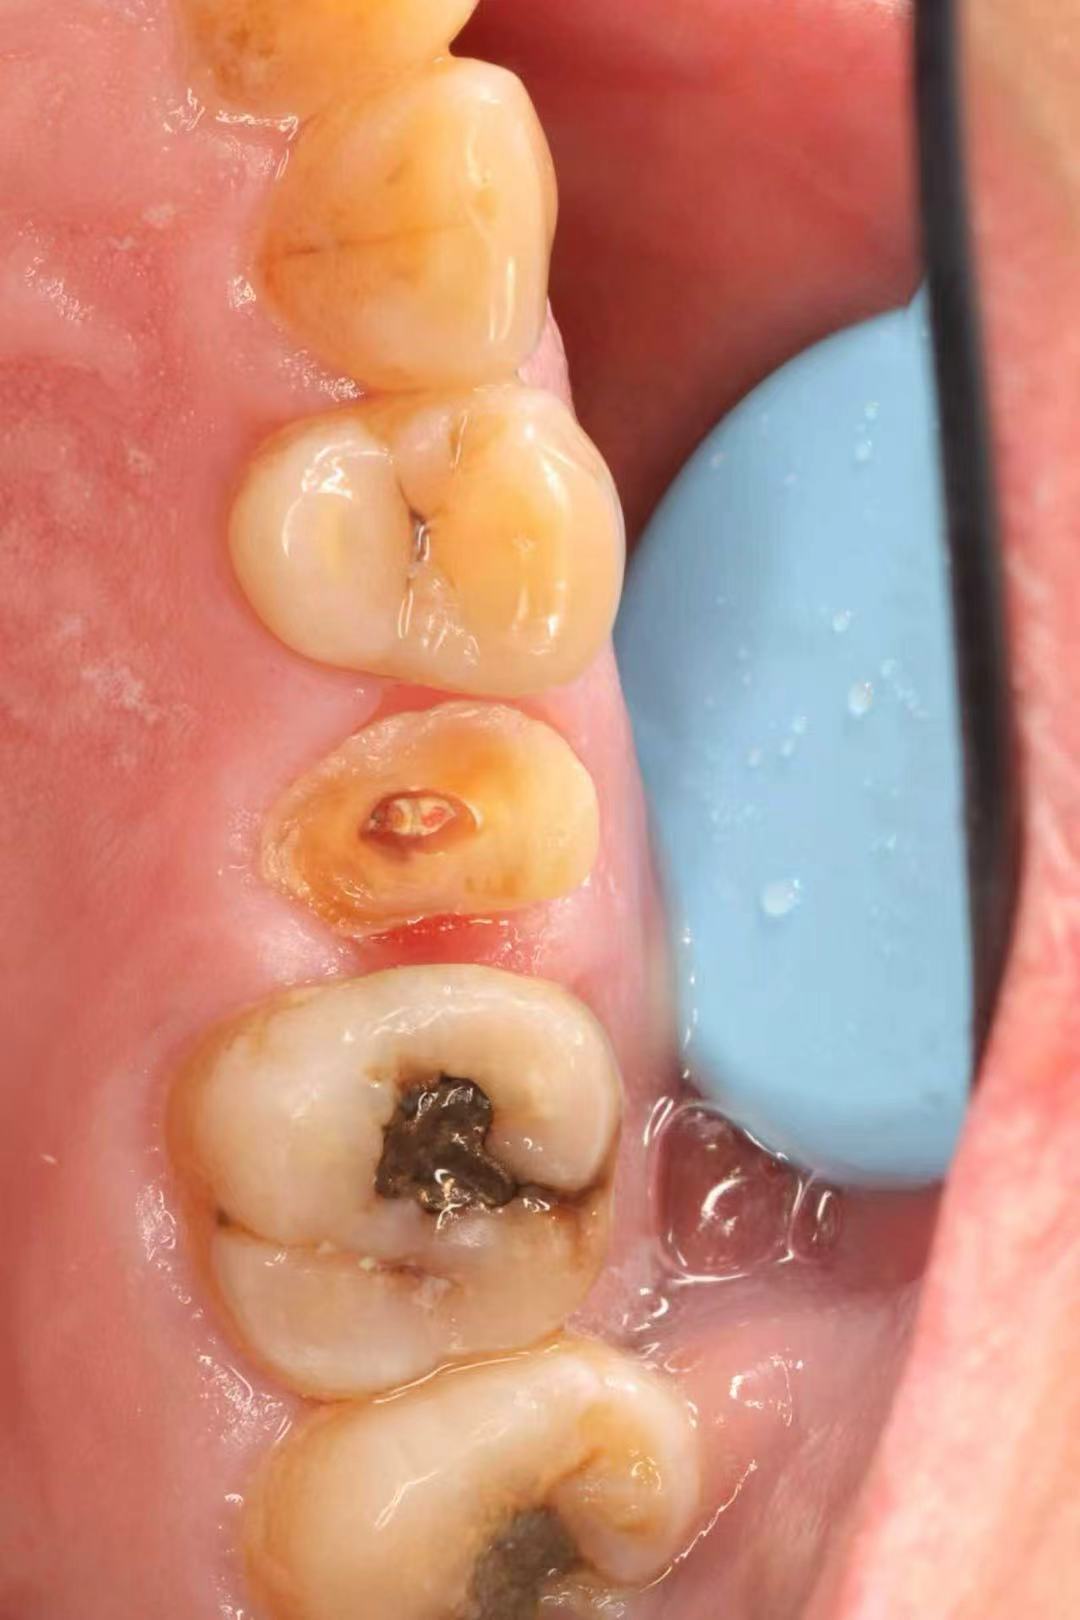

June 20, 2025: The patient's chief complaint is that endodontic treatment was performed on the right maxillary posterior tooth abroad, and a deep carious lesion has been recently detected, requiring restoration. The following are the intraoral photographs taken upon the patient's first visit: a large carious lesion is visible on the occlusal surface of tooth 15 (FDI numbering), with only the buccal wall remaining. Percussion test and cold-hot stimulation test showed no response, and yellow obturation material is visible at the root canal orifices.